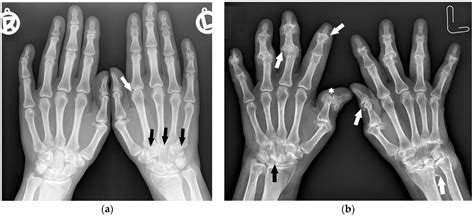

• Pathological Changes: Diseases or injuries can alter the normal anatomy, making it harder to identify sex-specific features.

• Overlapping Features: In some cases, the features may overlap, making it difficult to distinguish between sexes.